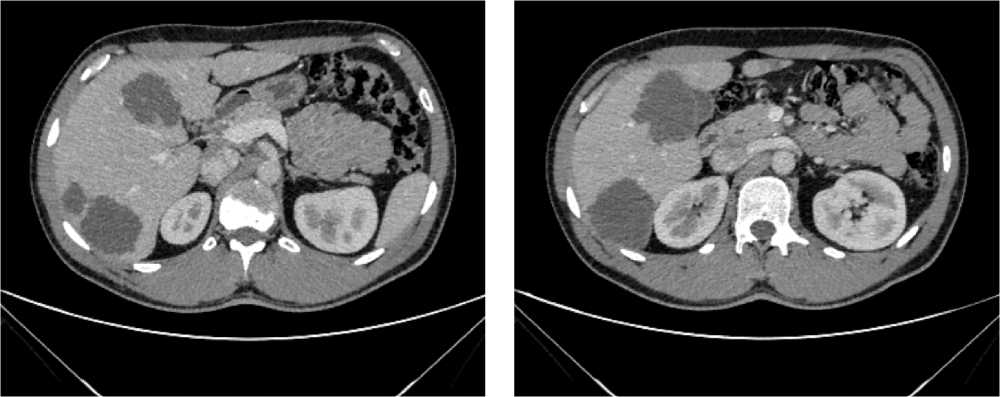

Выполнена компьютерная томография (КТ) органов грудной клетки, брюшной полости в июле 2019 г. Инфильтративных изменений в легких не обнаружено. Выявлено новообразование антрального отдела, малой кривизны и передней стенки желудка, распространяющееся на заднюю стенку, преимущественно на препилорический отдел. Имелись признаки локального перехода образования на большой сальник, гепатодуоденальную связку с периваскулярным ростом и признаками лимфоваскулярной инвазии. Многочисленные забрюшинные ЛУ сливались между собой в конгломераты размерами до 40 × 29 мм с частичным вовлечением почечных артерий. Также билобарно обнаружены немногочисленные очаговые образования в печени до 10 мм. Высказано подозрение на перитонеальный канцероматоз (рис. 3).

Рис. 3. Результаты компьютерной томографии органов брюшной полости у пациента 80 лет с диагнозом метастатический рак желудка с признаками микросателлитной нестабильности (июль 2019 г., до лечения)

Fig. 3. Results of a CT scan of the abdomen in an 80-year-old patient with metastatic MSI-H gastric cancer (July 2019, before treatment)

В результате обследования был установлен диагноз рака антрального отдела желудка (c)T4аN3вM1. По решению онкологического консилиума, учитывающего молекулярно-генетический профиль опухоли, а также возраст пациента, выраженность сопутствующей патологии (в анамнезе острое нарушение мозгового кровообращения (ОНМК), острый инфаркт миокарда (ОИМ), фибрилляция предсердий (ФП), постоянная форма), ограничивающей проведение ПХТ, была начата ИТ 1 линии пембролизумабом. С сентября 2019 г. по декабрь 2021 г. проведено 29 циклов ИТ 1 линии по схеме пембролизумаб в монорежиме с максимальным эффектом частичный регресс (рис. 4). Осложнений лечения не зарегистрировано.

Рис. 4. Частичный регресс по данным компьютерной томографии органов брюшной полости на фоне иммунотерапии пембролизумабом у пациента 81 года с диагнозом метастатический рак желудка с признаками микросателлитной нестабильности (декабрь 2021 г.; выживаемость без прогрессирования составила 25+ мес.)

Fig. 4. Partial response according to abdominal CT scan during immunotherapy with pembrolizumab in an 81-year-old patient diagnosed with MSI-H metastatic gastric cancer (December 2021; progression-free survival was 25+ months)